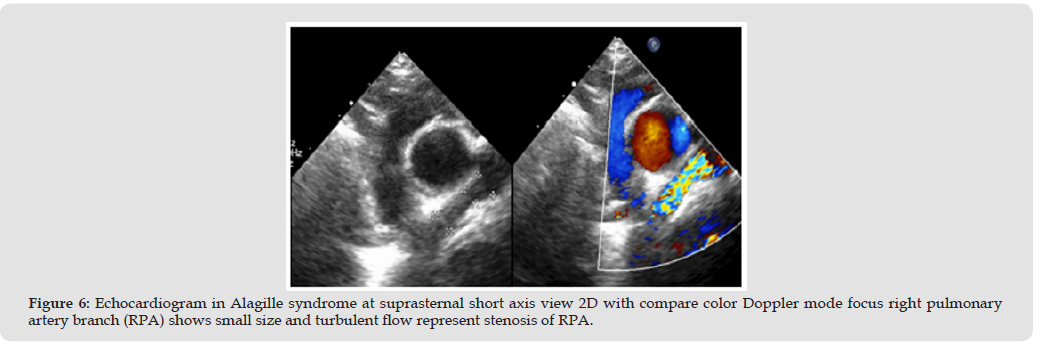

Alagille syndrome have main condition associate with cardiac are right side heart obstruction such as peripheral pulmonary artery stenosis (PPS). PPS was a common problem and cause for check echocardiography, lead to right heart hypertrophy or pressure elevated and relate to cyanotic signs in some case [7] (Figure 5) The remodeling of vascular intima, tunica media and adventitia lead to not progression of pulmonary artery branches size [8] In normal population, the echocardiography uses McGoon ratio for assessing PA size compare with abdominal descending aorta [9] If McGoon ratio = RPA+LPA/DAo has a value greater than 1.5 or 2.0 indicate to good size of the pulmonary artery [10] If z-score less than -2 may be considering pulmonary artery size abnormal or small, and need to measure pressure gradients across of dual branches, main pulmonary artery, and annulus valve of pulmonic if greater than 60 mm Hg May be considered severe stenosis [11,12] (Figure 6) However, the parasternal short axis of aortic valve level view focusing MPA, PV, and PA branches was a necessary view of measure size and PG across due to the direction of blood flow parallel the echo beam. In the children have a suprasternal long and short axis view is necessary window identified pulmonary artery structure, confluence appearance and size. Especially if we keep transducer marker to the left of the patient about 3 o’clock direction posterior angulation, this view able to visuals the first-loba branches of RPA too. (Figures 7 & 8).